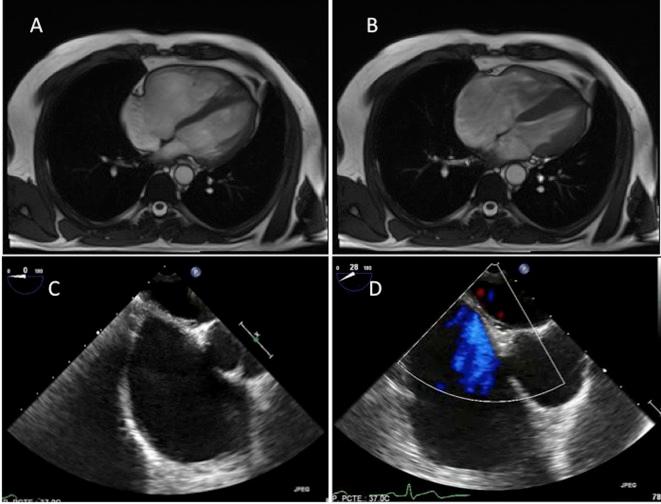

Because of an incomplete right bundle branch block, a severe right ventricular dilatation with no left ventricular cardiomyopathy was found in a 44-year-old man. Magnetic resonance and transesophageal echocardiography confirmed the finding and these tests also failed to find any potential cause. A pulmonary hemodynamic study and a coronary angiography were strictly normal. Lastly pulmonary function tests and a pulmonary angiography were performed, which did not find any lung disease causing the right ventricular dilatation. The patient was catalogued as an early stage of an idiopathic form of right ventricular dilated cardiomyopathy.